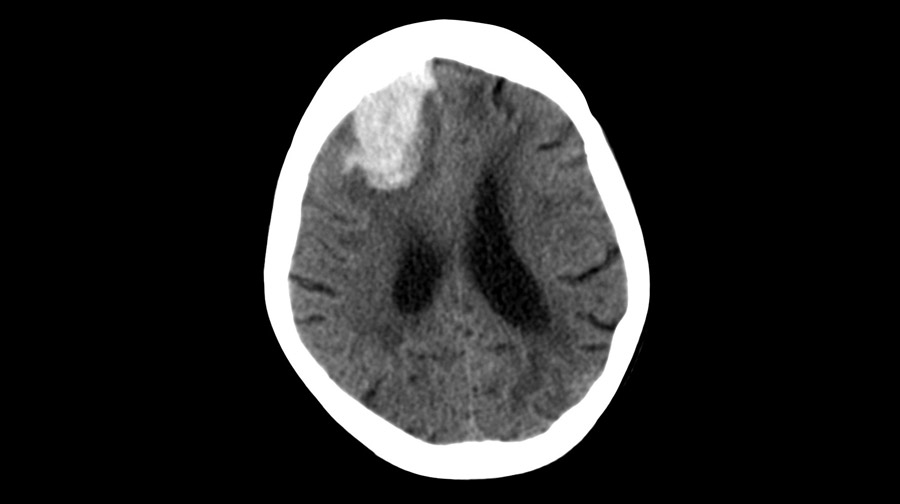

Eliminación temprana mínimamente invasiva de hemorragia intracerebral

11 abril 2024

En los pacientes en quienes la cirugía se pudo realizar dentro de las 24 horas posteriores a una hemorragia intracerebral aguda, la evacuación mínimamente invasiva del hematoma produjo mejores resultados funcionales a los 180 días que el  tratamiento médico basado en guías. El efecto de la cirugía parece atribuirse a la intervención de las hemorragias lobares. New England Journal of Medicine, 10 de abril de 2024.